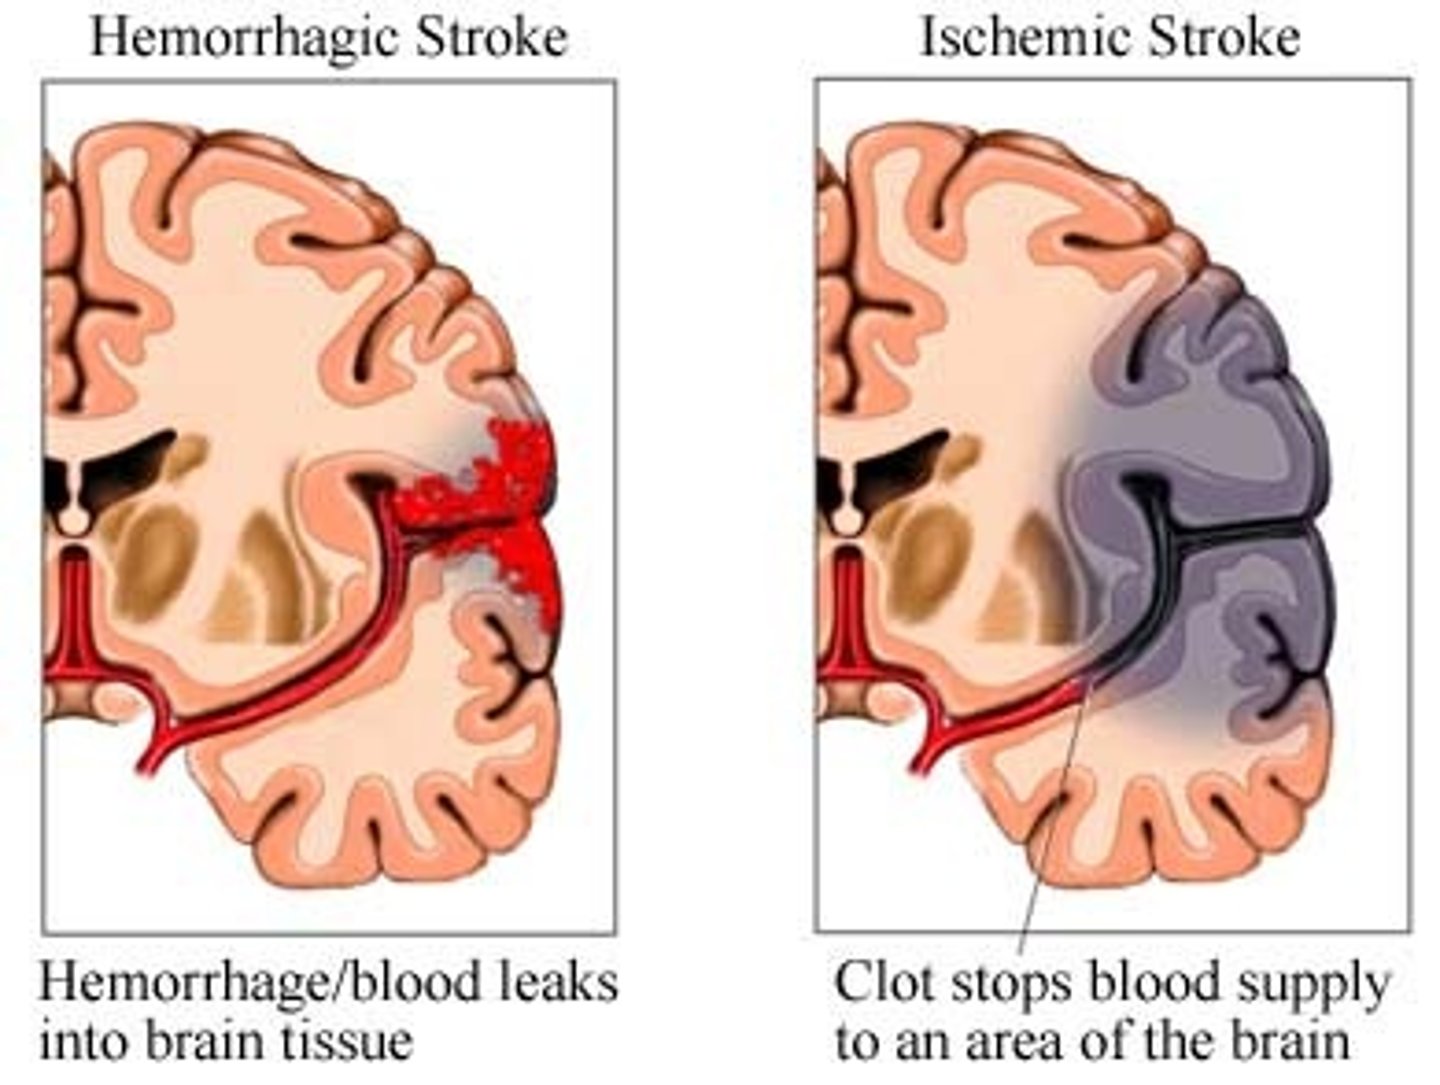

Cerebrovascular Accidents (CVAs and Strokes)

1)Death of brain tissue because of blood depravation,

2) Causes: Hemorrhagic & Ischemic

3) The glutamate cascade which lead to neural frying

-Rationale for rapid treatment